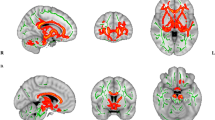

Peterson BS et al. (2002) A functional MRI study of language processing and cognitive outcome in prematurely born children. Pediatrics 110: 1153–1162

Ment LR et al. (2006) Cortical recruitment patterns in children born prematurely compared with control children druing a passive listening functional magnetic resonance imaging task. J Pediatr 149: 490–498